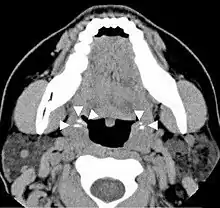

CT scan of tonsilloliths

Diagnosis is usually made upon inspection. Tonsilloliths are difficult to diagnose in the absence of clear manifestations, and often constitute casual findings of routine radiological studies. The cause of tonsil stones can include a multitude of sources from bacterial infections, streptococcus bacteria, viral infections, adenoviruses, influenza virus, enteroviruses and parainfluenza virus.[15]